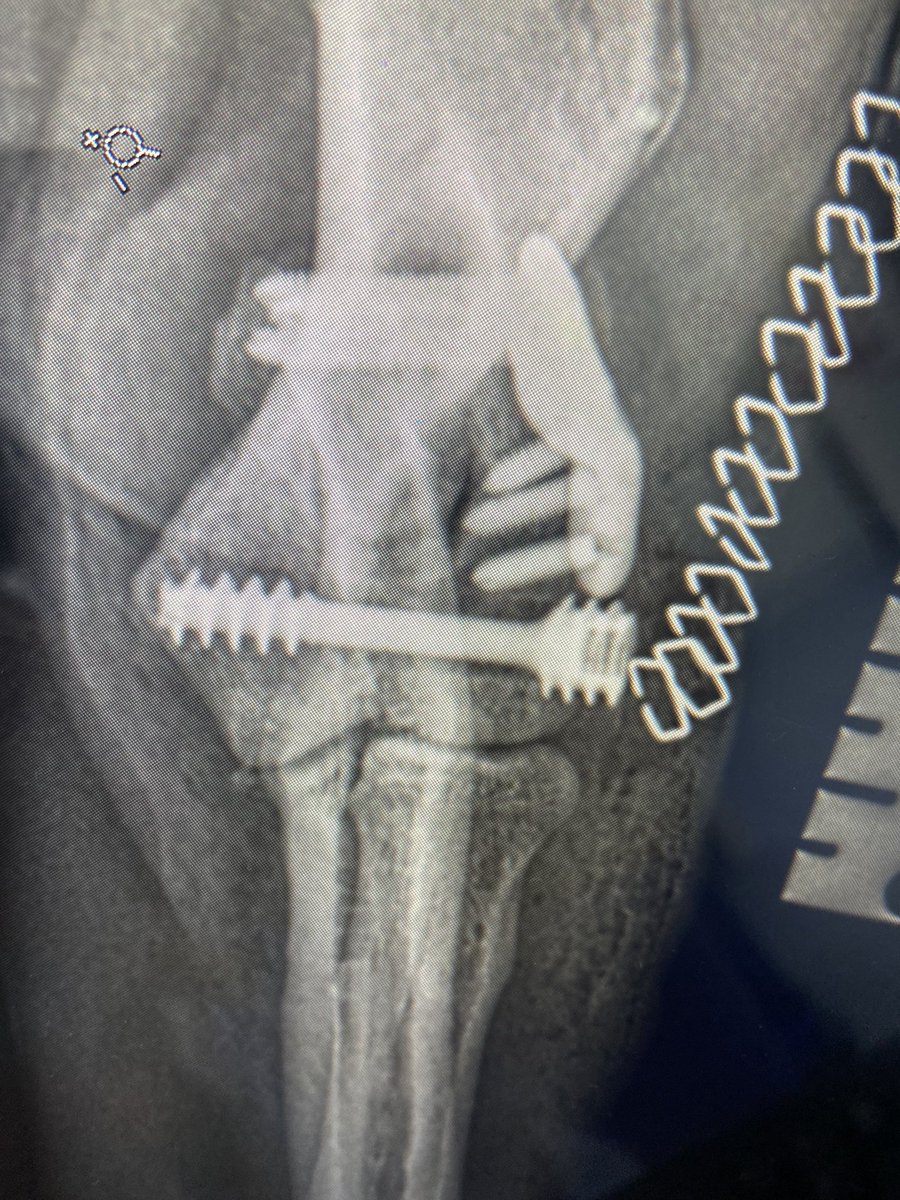

First there was one; now there are three. Beautiful titanium alloy headless, self-compressing screws for humeral intracondylar fissure repair in dogs as part of the Humeral Intracondylar Repair System Fusion Implants VeterinaryTissueBank Ben Walton B Duncan X Lascelles Vet Ortho Society

First there was one; now there are three. Beautiful titanium alloy headless, self-compressing screws for humeral intracondylar fissure repair in dogs as part of the Humeral Intracondylar Repair System <a href="/FusionImplants/">Fusion Implants</a> <a href="/veterinarytbank/">VeterinaryTissueBank</a> <a href="/m_ben_w/">Ben Walton</a> <a href="/bdxlascelles/">B Duncan X Lascelles</a> <a href="/vosdvm/">Vet Ortho Society</a>